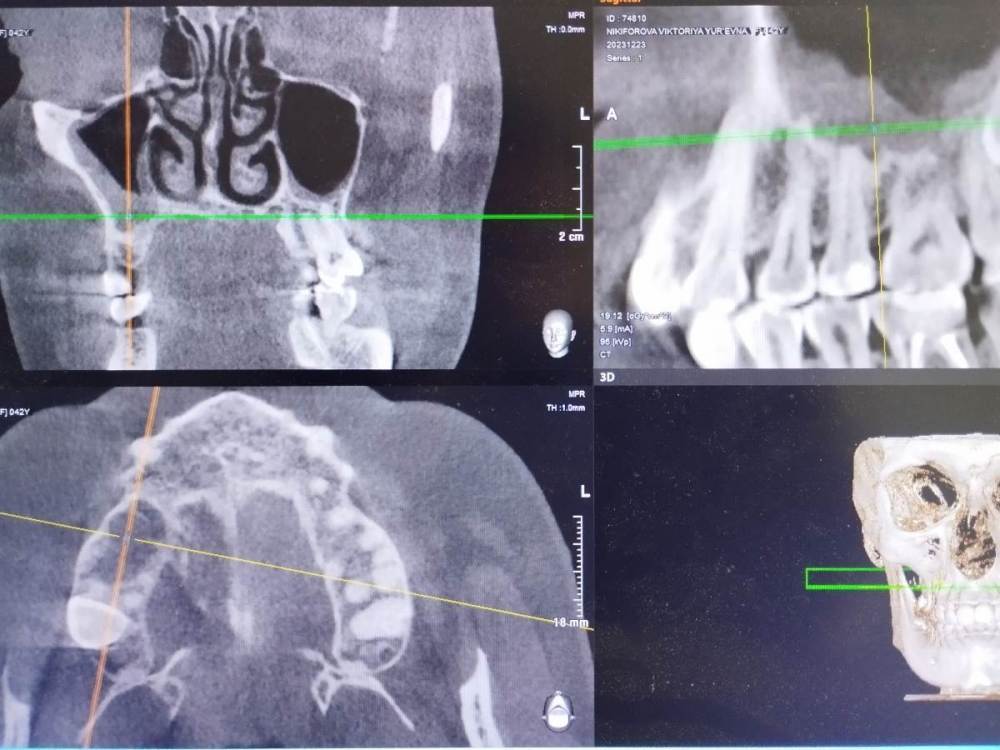

Здравствуйте! Врач говорит, что нужно лечить каналы зуба. Зуб под пломбой более 10 лет. Не беспокоит. Доктор прав?

Здравствуйте. Похоже, что да. Но фото размытые (потому что сфотографированы прямо с экрана. Лучше делать скриншоты, а ещё лучше выложить КТ целиком) и плохо понятно.